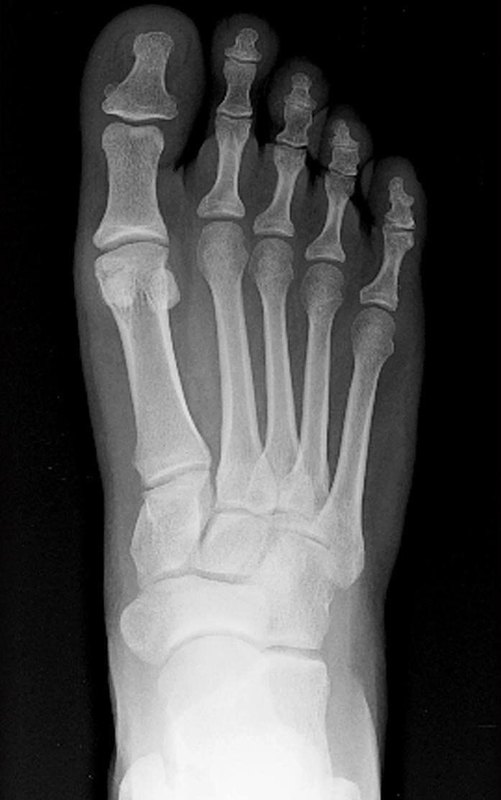

腳趾骨折的發(fā)生在臨床上病人發(fā)生腳趾骨折是一種比較常見(jiàn)的病癥,原因多數(shù)是由于受到直接外力導(dǎo)致的。病人發(fā)生腳趾骨折后,在具體的臨床癥狀上,首先病人會(huì)感覺(jué)腳趾部位有針刺樣疼痛,而且疼痛較重,局部會(huì)有廣泛性腫脹,壓痛陽(yáng)性,可以觸及明顯的異?;顒?dòng)或者骨擦音存在,而且腳趾關(guān)節(jié)的功能活動(dòng)受限,不能負(fù)重行走,有骨折移位的患者,在外觀上會(huì)產(chǎn)生畸形的現(xiàn)象。可以拍攝腳趾部位的X光片,就能夠明確看到骨折的存在和骨折程度。 腳趾骨折多長(zhǎng)時(shí)間可以下地走路?腳趾骨折多半1個(gè)月到1個(gè)半月可以下地負(fù)重。 人體骨折愈合時(shí)間跟骨頭的形態(tài)、結(jié)構(gòu)有密切的關(guān)系,大致是越小的骨頭愈合越快。 腳趾骨比較細(xì)小,骨折后1個(gè)來(lái)月就基本愈合了。一般術(shù)后4周就應(yīng)該給予復(fù)查X線片。如果X線片可以看到有骨折線模糊,或者有骨痂生長(zhǎng),就可以拆除外固定,開(kāi)始下地負(fù)重行走功能鍛煉,如果4周還沒(méi)看到,有很明顯的骨折線模糊,還是必須要以休息為主,繼續(xù)外固定,再過(guò)2周,再?gòu)?fù)查線片。如果看到有骨折線模糊,就可以開(kāi)始下地行走功能鍛煉,開(kāi)始下地的時(shí)候盡量不要完全負(fù)重,以部分負(fù)重為主,最好還是單拐杖行走,等完全可以受力之后,才可以放棄拐杖正常走路 當(dāng)然,下地前一定要到醫(yī)院復(fù)查X光片,給醫(yī)生看過(guò),證實(shí)骨折愈合了才能逐步開(kāi)始負(fù)重。畢竟傷情千差萬(wàn)別,每個(gè)人的具體情況都不盡相同,“個(gè)性化”治療絕不是一句空話哦。 ps:文中部分圖片來(lái)自網(wǎng)絡(luò),如有侵權(quán)請(qǐng)聯(lián)系刪除,謝謝!